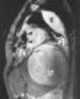

Fluid-filled bronchial cyst